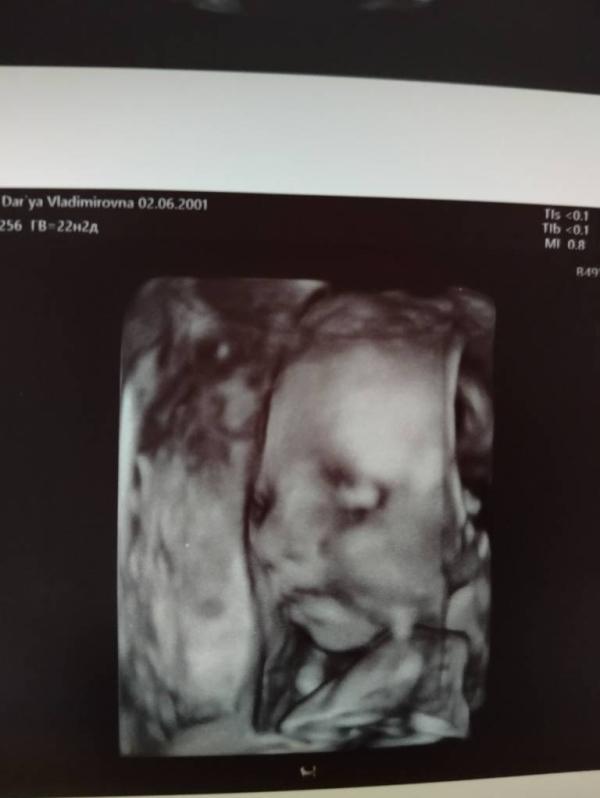

Наш маленький малыш🙏❤️

Сходила на узи к Гридиной, нос НОРМА, дмжп НЕТУ, кист в головном мозге НЕТУ.

Но была найдена киста около головы за ушком(((

Пока сложно сказать, почему она появилась, нужно смотреть в динамике😔